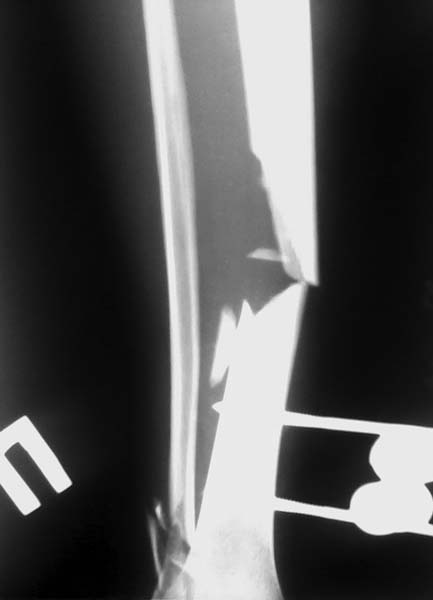

Доброго времени суток уважаемые коллеги!! Поступил пациент, 43-х лет. Травма в ДТП 18.04.

Открытый перелом обеих костей правой голени. Отломок потеряли при доставке в больницу

"где-то в машине". Как вести дальше?? Вариантов несколько: аппарат внешней фиксации с

последующим выращиванием регенерата, либо дождаться заживления раны и произвести БИОС с

костной аутопластикой. Откуда лучше взять аутотрансплантат? Пациент работающий и ему

очень важна как можно более ранняя ходьба.